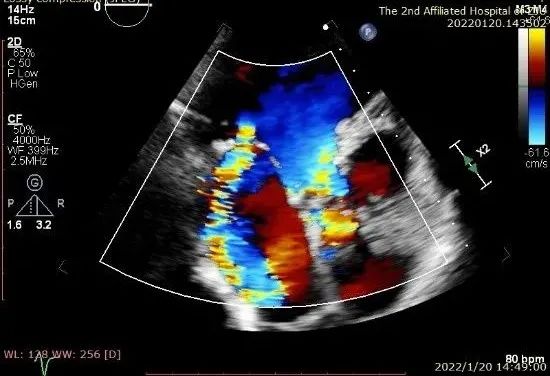

患者二术后二尖瓣零反流